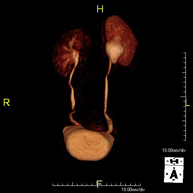

Prova diagnòstica no invasiva que consisteix en l'obtenció d'imatges d'alta definició anatòmica del fetge mitjançant l'ús d'un camp electromagnètic i ones de ràdio (amb un emissor i un receptor). No utilitza radiació ionitzant. Es realitza per estudiar qualsevol lesió localitzada en el fetge. Normalment es requereix l'ús de contrast paramagnètic (Gadolini) per caracteritzar les lesions. És necessari realitzat la prova en dejú (6 hores). - RM de Ronyons

Prova diagnòstica no invasiva que consisteix en l'obtenció d'imatges d'alta definició anatòmica d'ambdós ronyons mitjançant l'ús d'un camp electromagnètic i ones de ràdio (amb un emissor i un receptor). No utilitza radiació ionitzant. Es realitza per estudiar qualsevol lesió localitzada en ambdós ronyons. Normalment es requereix l'ús de contrast paramagnètic (Gadolini) per caracteritzar les lesions. - RM Glándulas Suprarrenales